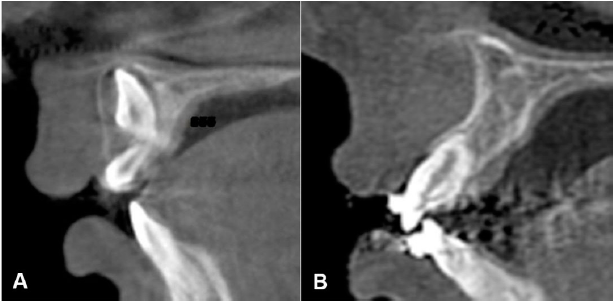

Paciente de género masculino de 8 años de edad, sin antecedentes mórbidos. Perfil convexo, clase II esqueletal. En el análisis intraoral se observó dentición mixta primera fase, diente parcialmente erupcionado en zona de diente 11, diente 21 mesiorotado, distoclusión molar bilateral, discrepancia óseo-dentoalveolar severa superior y moderada inferior, relación transversal desfavorable, líneas medias dentarias centradas (Figura 4. A-D). En el análisis con CBCT, realizado con el software Nemotec ® se observó el diente 11 en evolución intraósea en una posición alta, perpendicular al plano oclusal con formación radicular incompleta, ubicado hacia vestibular, con una distancia de 19.57 milímetros al borde incisal del incisivo central contralateral, y la presencia de un diente supernumerario parcialmente erupcionado, de forma coronaria cónica en zona del diente 11 (Figura 5. A-B).

Figura 5 Imágenes tomográficas. A. Corte sagital inicial de diente 11 evaluado en CBCT. B. Representación tridimensional de posición inicial de diente 11 evaluado en CBCT, vista frontal.

Los resultados obtenidos son favorables para ambos casos descritos. Respecto al caso número uno, en el control tomográfico el diente 21 presenta un soporte periodontal favorable, paralelismo radicular y proporción corono radicular 1:1 (Figura 7. A-B). Respecto al caso número dos, en el control tomográfico, el diente 11 presenta una posición adecuada en la arcada, una longitud radicular disminuida y un soporte periodontal con pronóstico reservado (Figura 8. A-B). Ambos casos clínicamente presentan un posicionamiento adecuado en el arco y no presentaron defectos mucogingivales posterior a la tracción.